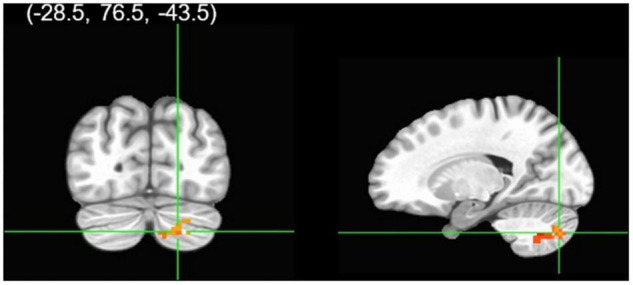

Cannabis users, relative to controls, demonstrated significantly less left [t(61) = −3.08, beta = −0.42, p = 0.003] and right [t(61) = −3.07, beta = −0.42, p = 0.003] rACC activation during fearful-calm No-go (Figure 1). Gender did not moderate the relationship between cannabis group and left [t(60) = 0.75, beta = 0.09, p = 0.46] or right [t(60) = 0.55, beta = 0.07, p = 0.58] rACC activation. Greater past year alcohol use significantly predicted stronger right rACC activation [t(61) = 2.13, beta = 0.29, p = 0.04] (see Table 2).

Cannabis and cannabis × gender did not significantly predict clusters functionally connected to the right rACC during successful Calm No-go trials. Despite no cannabis × gender interaction, within a contrast of cannabis-using males compared to cannabis-using females, males demonstrated significantly greater connectivity relative to females between the right rACC and a cluster in the right cerebellum (Table 2 and Figures 2, 3). Within non-users, gender was not related to right rACC connectivity.

The current study is the first to assess relationships between cannabis use, gender, and rACC activation and functional connectivity during an emotional response inhibition task. It was found that abstinent cannabis users, relative to non-using controls, had significantly decreased left and right rACC activation during successful response inhibition upon presentation of fearful faces. Regarding connectivity results, there were no significant differences between abstinent cannabis users and controls in rACC connectivity during fearful or calm response inhibition. Further, group level moderation by gender was non-significant. However, follow-up contrasts revealed that abstinent cannabis-using males, relative to cannabis-using females, demonstrated greater right rACC and right cerebellum connectivity during successful calm No-go trials. Within non-users, gender was not related to rACC connectivity. Interestingly, findings were unrelated to current levels of perceived stress.

While gender did not significantly moderate the relationship between cannabis use and rACC connectivity during either fearful or calm response inhibition, within a contrast of only the cannabis-using group, gender was related to rACC connectivity. Specifically, cannabis-using males, relative to females, demonstrated greater connectivity between the right rACC and right cerebellum during Calm No-go response inhibition. Because no gender interaction was observed, this is considered a marginal finding useful for future directions and should be replicated. On inspection (Figure 3), males’ right rACC and right cerebellum connectivity during Calm response inhibition more closely resembles connectivity of male and female controls. This marginal finding suggests that females may be more vulnerable to the effects of cannabis on cognition and affect, consistent with previous research (ref. 54, ref. 82, ref. 84–ref. 86). This may potentially be due to differences in gender-specific use patterns (ref. 117), though, warrants future investigation in larger sample sizes that can conduct gender-specific analyses. Related to the present findings, the cerebellum has a particularly high density of CB1 receptors and female rats have exhibited increased vulnerability to reduced CB1 receptor expression in the cerebellum under repeated stress (ref. 6, ref. 7, ref. 118). Alternatively, it is possible that increased rACC and cerebellum connectivity in cannabis-using males indicates an over-reliance on the cerebellum, which has been observed in substance users during other cognitive tasks (ref. 119–ref. 122). Thus, cannabis use may differentially impact male and female rACC-cerebellar circuitry during response inhibition. Again, this finding should be replicated in a larger sample.